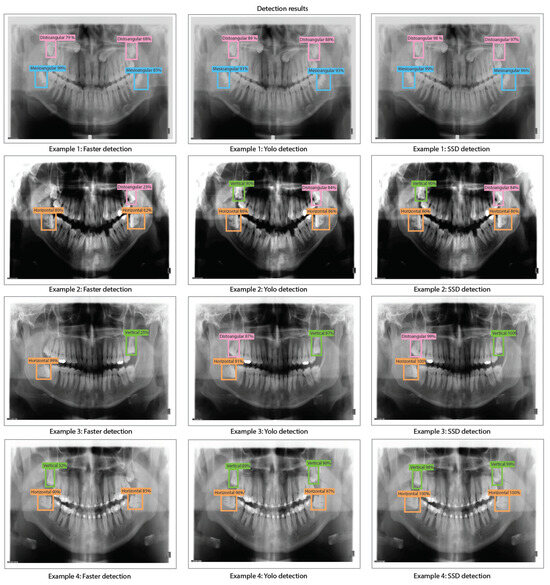

- We train, validate, and test DL-based object detection algorithms based on the You Only Look Once V2 (or YOLO V2), Faster Region-Convolutional Neural Network (Faster R-CNN), and Single Shot Multi-box detector (SSD). We compare the performance of each object detection model by using ResNet-18, ResNet-50, and ResNet-101 for the feature extraction stage of each detector.

- We present our results by using precision-recall curves in the proposed dataset. In addition, we evaluated bias, variance, overfitting, and underfitting for each model trained based on YOLO V2, Faster R-CNN, and SSD for the proposed dataset along with detection results and comparison tables of detection percentages.

- We obtained the best results for Faster R-CNN using ResNet-18 were reached in test 2 (training: 25%, validation: 24%, and testing: 39%). For YOLO V2 using ResNet-18, the best result is test 10 (training: 99%, validation: 90%, and testing: 96%). Finally, for the SSD model using ResNet-18, the best result was in test 12 (training: 87%, validation: 82%, and testing: 81%). This indicates that the best model for this experiment set is YOLO V2 using ResNet-18 with the hyper-parameter configuration of test 10. This model has a low bias and variance, demonstrating high generalizing capabilities (no overfitting) since the accuracy is barely reduced from training to validation and testing. We can observe the training, validation, and testing results for models obtained in tests 2, 10, and 12 in Figure 10, in which we present the precision-recall curves for such models.

- We obtained the best results for YOLO V2 using ResNet-50 in test 18 (training: 99%, validation: 89%, and testing: 95%). For the SSD model using ResNet-50, the best result was in test 9 (training: 88%, validation: 91%, and testing: 88%). This indicates that the best model for this set of experiments is YOLO V2 using ResNet-50 with the hyper-parameter configuration of test 18. This model has a low bias and variance, demonstrating high generalizing capabilities (no overfitting) since the accuracy is barely reduced from training to validation and testing. We can observe the training, validation, and testing results for models obtained in tests 11, 18, and 9 in Figure 12 in which we present the precision-recall curves for both models.

- We obtained the best results for YOLO V2 using ResNet-101 in test 11 (training: 99%, validation: 92%, and testing: 99%). For the SSD model using ResNet-101, the best result was in test 12 (training: 88%, validation: 90%, and testing: 89%). This indicates that the best model for this set of experiments is YOLO V2 using ResNet-101 with the hyper-parameter configuration of test 11. This model has a low bias and variance, demonstrating high generalizing capabilities (no overfitting) since the accuracy is barely reduced from training to validation and testing. We can observe the training, validation, and testing results for models obtained in tests 5, 11, and 12 in Figure 14 in which we present the precision-recall curves for both models.

- During the implementation of third-molar detection algorithms using different detection models and ResNet architectures, it can be observed that YOLO V2 is the model that stands out in terms of both accuracy and consistency during the training, validation, and testing stages. Therefore, the best results from our experiments were obtained by YOLO V2 using ResNet-18 (training: 99%, validation: 90%, and testing: 96%), YOLO V2 using ResNet-101 (training: 99%, validation: 92%, and testing: 99%), and YOLO V2 using ResNet-101 (training: 99%, validation: 92%, and testing: 99%), which indeed are very similar. These high accuracy results indicate that YOLO V2 is very effective for detecting third molar angles in our X-ray dataset distribution. On the other hand, the Faster R-CNN models with ResNet CNNs (ResNet-18, ResNet-50, and ResNet-101) possess underfitting problems for our X-ray dataset distribution. This might be because the Faster R-CNN is characterized by using an RPN (Region Proposal Network) stage. On the other hand, the SSD detection model has moderate accuracy across all ResNet architectures. Although SSD does not achieve the accuracy levels of YOLO V2, it produces reasonably consistent results, making it suitable for applications that require a balance of accuracy and detection speed (inference times less than 100 ms).

- Overall, we have demonstrated in this work that CNN-based object detection techniques can be used to detect third-molar angle detection based on Winter’s classification criterion. The categories that we detected are distoangular, vertical, mesioangular, and horizontal. To detect these categories, we have implemented several object detection methods, which are YOLO V2, Faster R-CNN, and SSD. Each of the mentioned object detection methods was trained by using ResNet-18, ResNet-50, and ResNet-101 as feature extraction methods, in which YOLO V2 with ResNet-18 obtained the best results (training: 99%, validation: 90%, and testing: 96%). These findings represent a promising solution for dentistry applications, such as improved diagnostic accuracy, more automated dental procedures, and even a possible training tool for educational applications. Moreover, we have presented a significant improvement compared to other works, that only train a single object detection method for different applications such as third molar detection and angle detection, tooth identification, caries detection, dental implant detection, and crown detection (see Table 7).